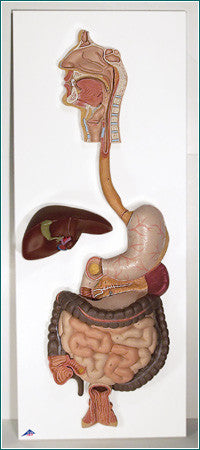

Anatomy

Anatomical models and charts by Body System or Anatomical Region for Nursing, Physical Therapy, and Medical Education.